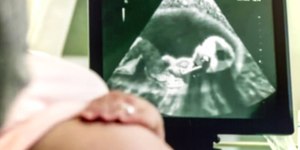

A dubladora e influenciadora Lhays Macedo, de 32 anos, vive um momento de alegria e realização. Após enfrentar quatro abortos espontâneos e receber o diagnóstico de trombofilia — condição que aumenta o risco de coágulos e dificulta a implantação do embrião —, ela anunciou sua segunda gestação. A futura mãe espera agora o primeiro menino, que se junta à primogênita Maria Bella, de apenas 1 ano.

Diante dessas dificuldades, a dubladora buscou acompanhamento médico especializado e ajustou o tratamento com anticoagulantes para reduzir os riscos associados à trombofilia. A estratégia deu certo: em fevereiro de 2024, Lhays engravidou novamente e deu à luz Maria Bella em novembro do mesmo ano.

A surpresa da nova gestação veio de forma mágica. Durante um cruzeiro da Disney, Lhays e o marido, o médico Yago Fernandes, optaram por revelar o sexo do bebê de maneira especial. O exame de sexagem fetal havia sido realizado com oito semanas de gestação, mas o casal decidiu esperar para descobrir a surpresa durante a viagem.